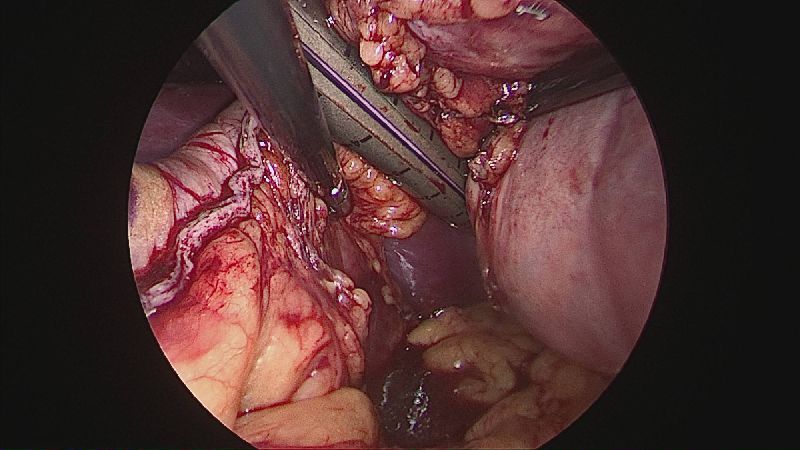

Operația ”de micșorare a stomacului” se realizează miniminvaziv (laparoscopic) și constă în îndepărtarea marii curburi gastrice cu păstrarea antrului gastric și a micii curburi sub forma unui tub calibrat pe o sondă.

Tehnica aduce beneficiile chirurgiei laparoscopice, durere redusă, externare în primele 48 ore de la intervenție. Avantajul său constă în confortul oferit pacientului care prezintă senzația de sațietate rapid prin umplerea unui stomac de doar 100 ml, reducerea senzației de foame prin suprimarea secreției de grelina. De asemenea, nu modifică traseul alimentelor, nu exclude segmente digestive din circuit și pierderea excesului ponderal poate ajunge până la 100%.